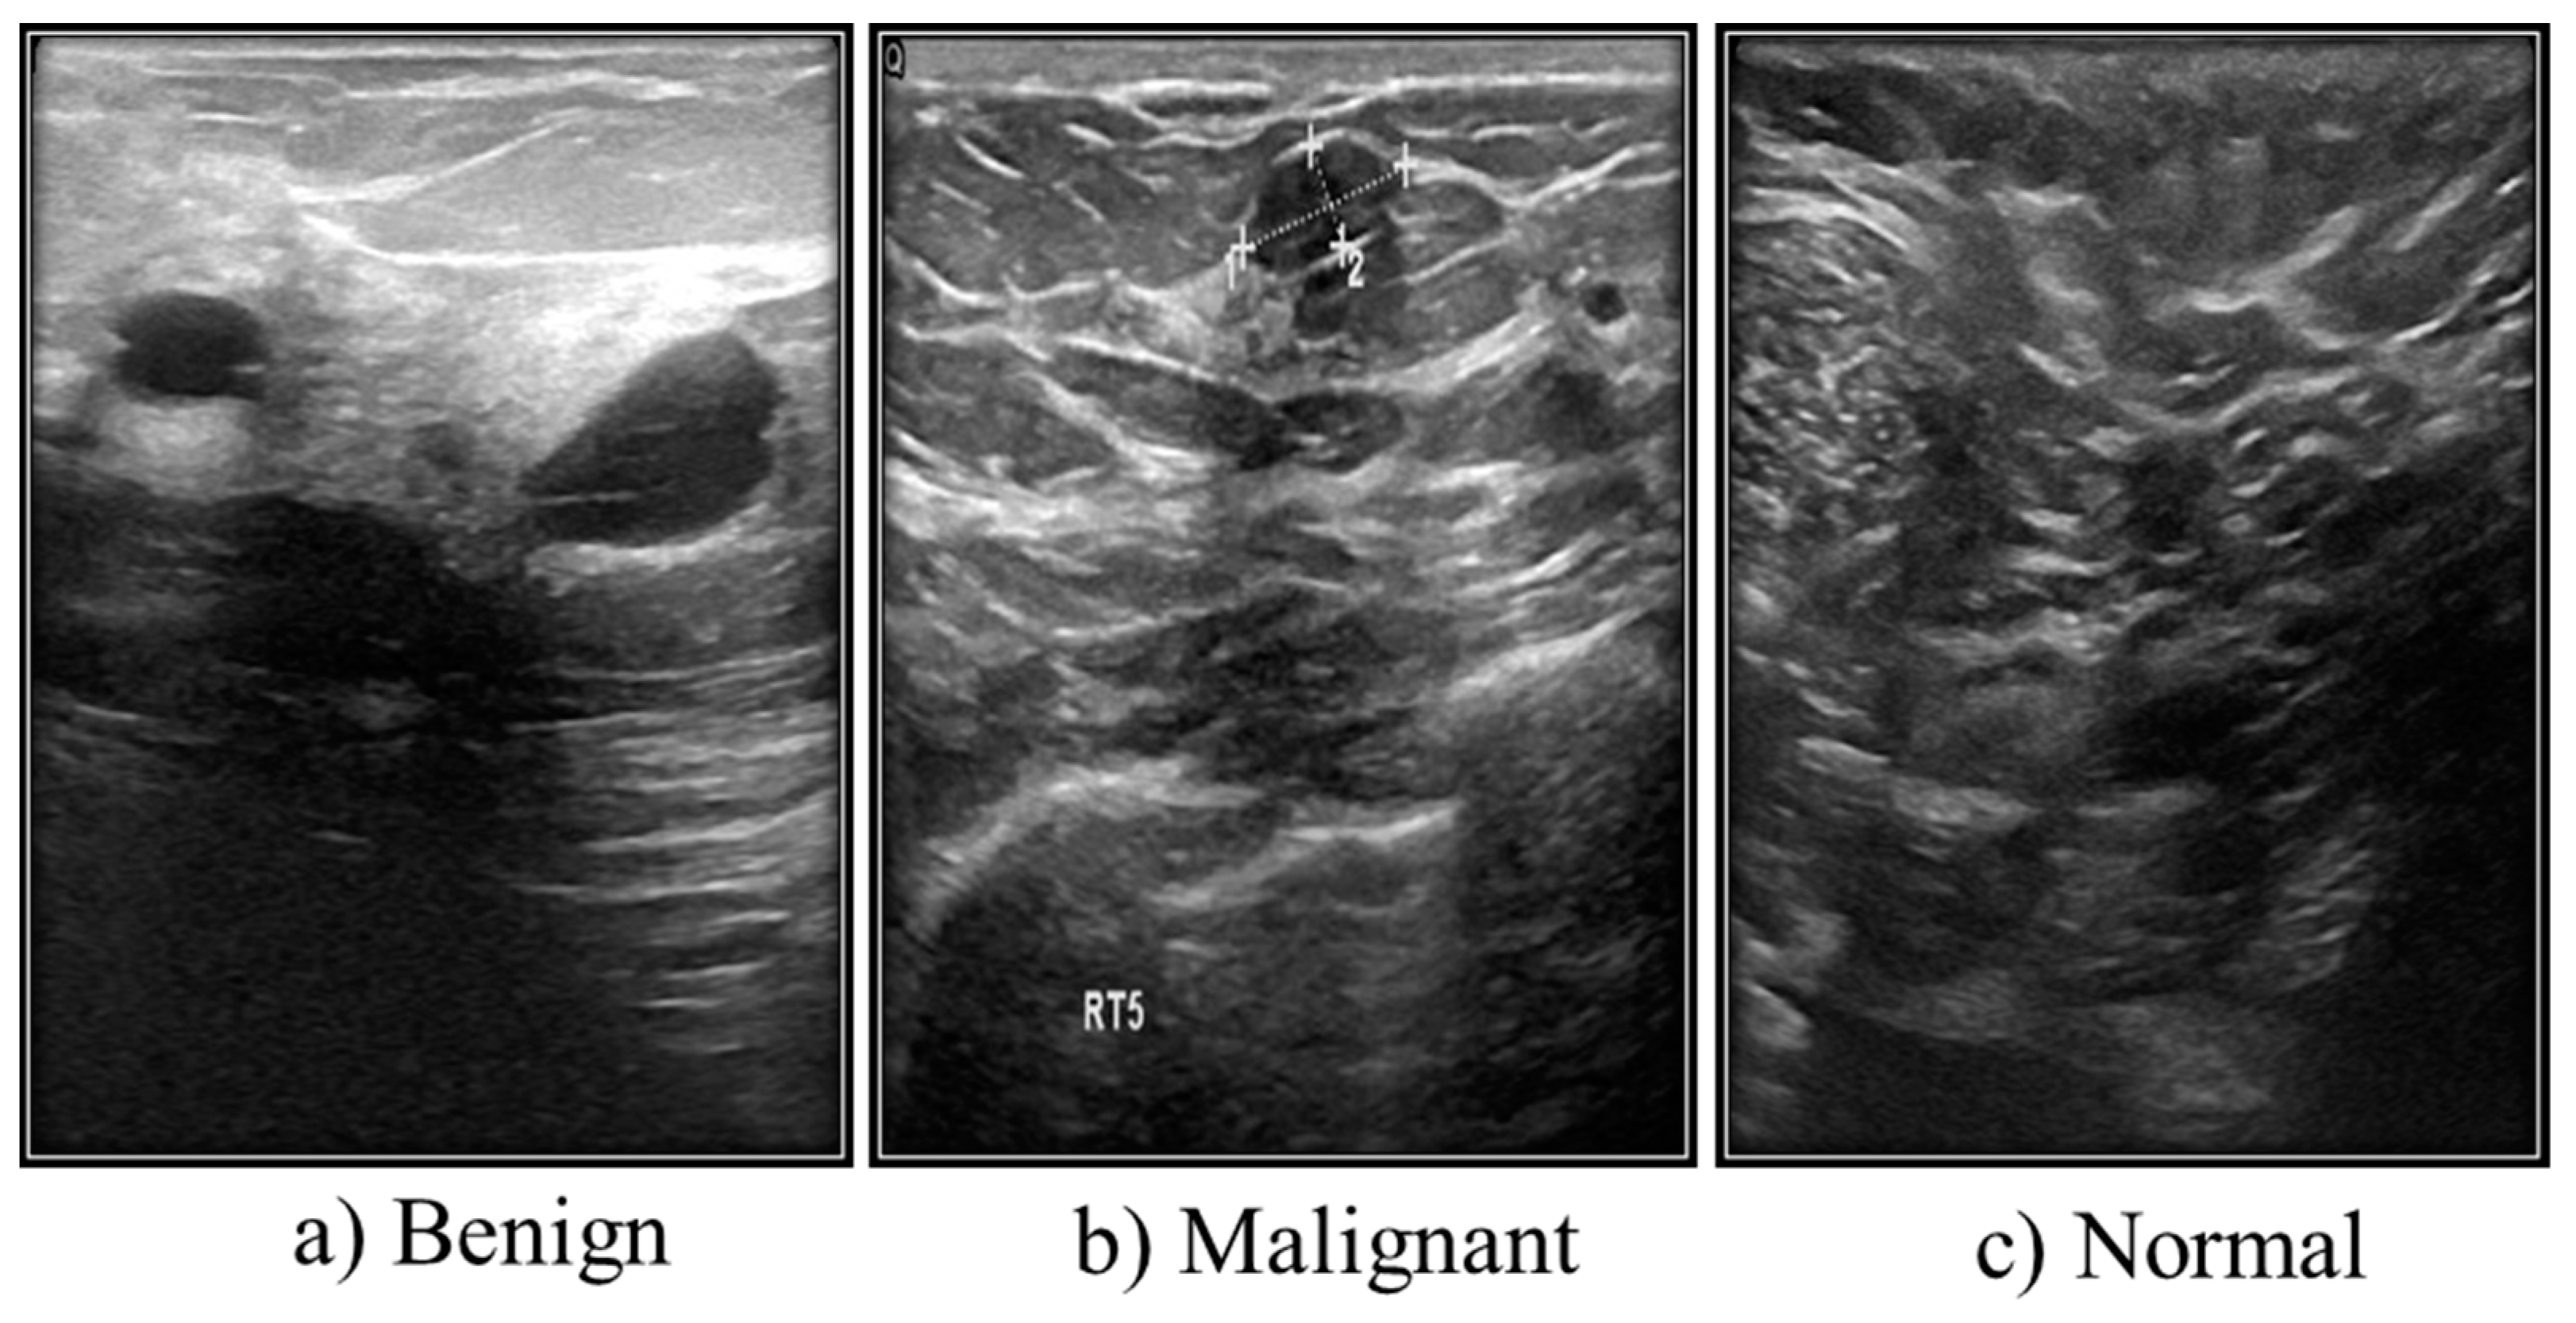

3.2. Ultrasound Images

| Case | Number of Images |

|---|---|

| Benign | 487 |

| Malignant | 210 |

| Normal | 133 |

| Total | 780 |